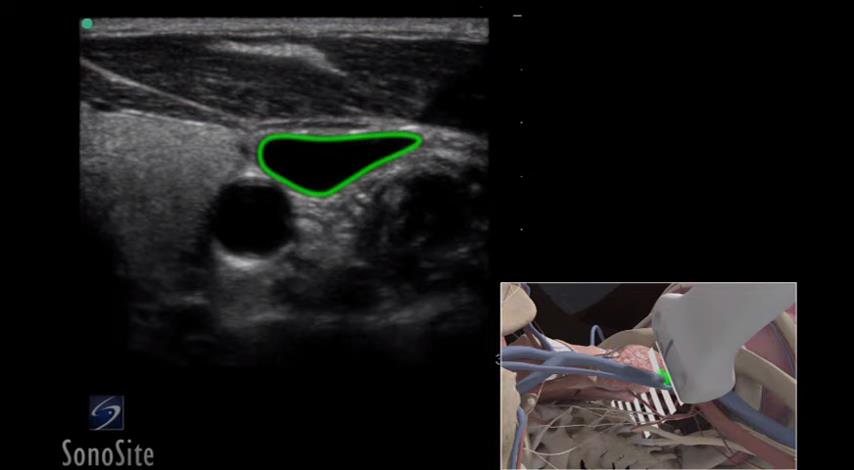

“剑突下四腔心”切面的获取

336 #心超